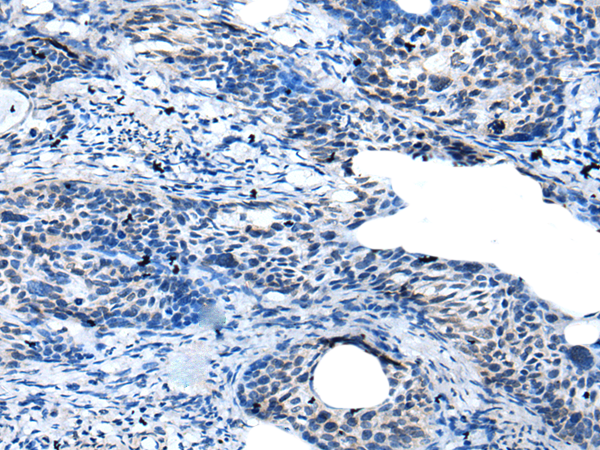

IHC positive control: |

Human cervical cancer |

IHC Recommend dilution: |

10-50 |